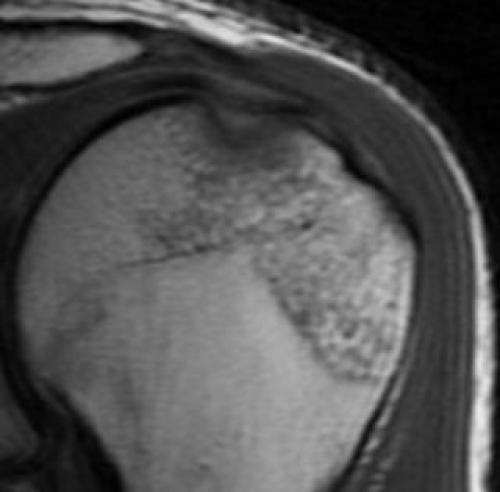

МРТ плечевого сустава. Корональные Т1-взвешенные МРТ. Переломы Хилла-Сакса и Банкарта.